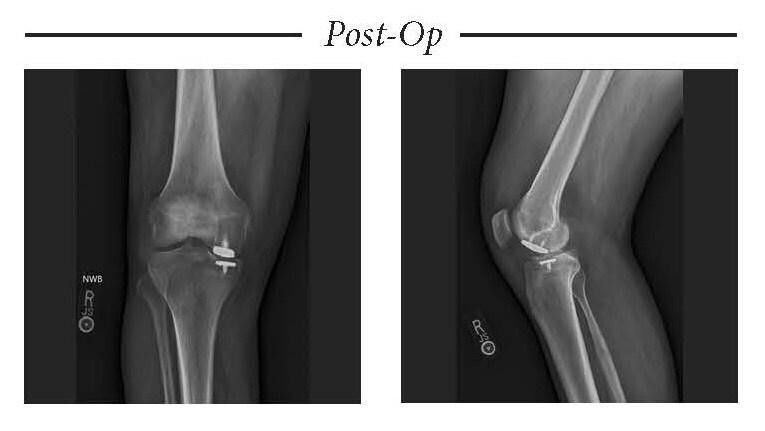

OvertureTi Knee Resurfacing System implants are designed specifically as an alternative when it is still too early for arthroplasty, but biological repair options are not viable for treating early osteoarthritis and focal cartilage lesions. The system is composed of femoral and tibial implants intended to be used in the partial replacement of the articular surfaces of the knee. These implants were designed with sizing options that allow the surgeon to replace only the diseased or damaged region of the joint while preserving healthy native cartilage and soft tissue. The procedure is referred to as Focalplasty®.

Overture’s technologically advanced, biocompatible implants have baseplates that are 3D printed, porous titanium to promote solid fixation; articulating surfaces for the femoral and tibial components are clinically proven titanium nitride and over-molded highly cross-linked Vitamin E treated polyethylene, respectively. The implants are a fraction of the cost of biological options.

The OvertureTi Knee Resurfacing System is 510(k) cleared by the United States Food and Drug Administration and available for immediate use, with all instrumentation sterile-packed for streamlined, single-use efficiency in the operating room.